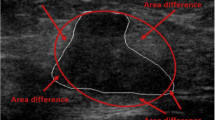

To determine which Breast Imaging Reporting and Data System (BI-RADS) descriptors for ultrasound are predictors for breast cancer using logistic regression (LR) analysis in conjunction with interobserver variability between breast radiologists, and to compare the performance of artificial neural network (ANN) and LR models in differentiation of benign and malignant breast masses. Five breast radiologists retrospectively reviewed 140 breast masses and described each lesion using BI-RADS lexicon and categorized final assessments. Interobserver agreements between the observers were measured by kappa statistics. The radiologists’ responses for BI-RADS were pooled. The data were divided randomly into train (n = 70) and test sets (n = 70). Using train set, optimal independent variables were determined by using LR analysis with forward stepwise selection. The LR and ANN models were constructed with the optimal independent variables and the biopsy results as dependent variable. Performances of the models and radiologists were evaluated on the test set using receiver-operating characteristic (ROC) analysis. Among BI-RADS descriptors, margin and boundary were determined as the predictors according to stepwise LR showing moderate interobserver agreement. Area under the ROC curves (AUC) for both of LR and ANN were 0.87 (95% CI, 0.77–0.94). AUCs for the five radiologists ranged 0.79–0.91. There was no significant difference in AUC values among the LR, ANN, and radiologists (p > 0.05). Margin and boundary were found as statistically significant predictors with good interobserver agreement. Use of the LR and ANN showed similar performance to that of the radiologists for differentiation of benign and malignant breast masses.